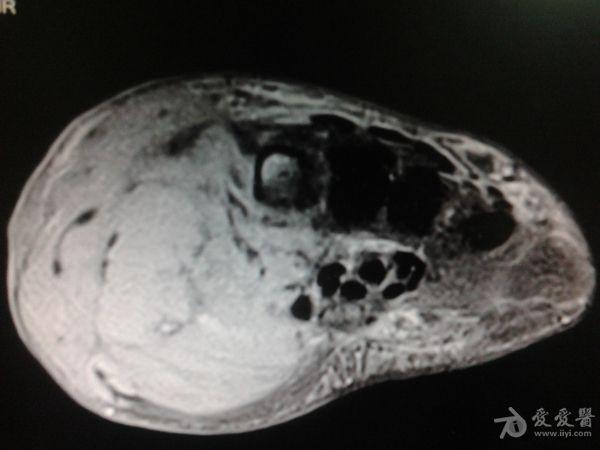

右第一掌骨、大多角骨肿瘤

男性患者,81岁,右手肿痛3个多月。无任何其它症状。体查:右手第一掌骨部肿胀明显,第一指活动受限,余四指活动可,腕关节活动小部分受限,活动时会痛。影像学检查如下。活检示:弥漫性大B细胞淋巴瘤。大家看看需不需要截肢?现在有人主张手术;有人主张不手术,直接化疗。大家有什么看法?